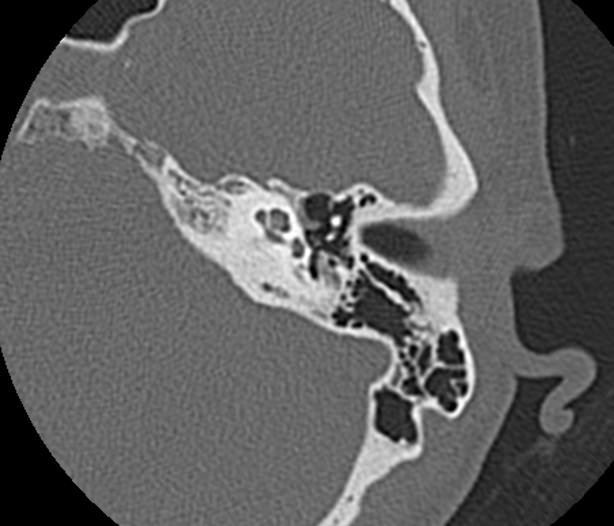

Мультиспиральная КТ позволяет детально визуализировать все вышеперечисленные анатомические структуры височных костей, диагностировать заболевания среднего и внутреннего уха.

КТ наиболее информативна при черепно-мозговых травмах, воспалительных заболеваниях уха, опухолевых процессах этой области. При компьютерной томографии возможно проследить ход барабанной перепонки, оценить структурность и положение слуховых косточек (молоточка, стремечка и наковальни), оценить объем и расположение содержимого в антральной клетке или ячейках сосцевидного отростка височной кости.

- показать четкую картину строения среднего уха.